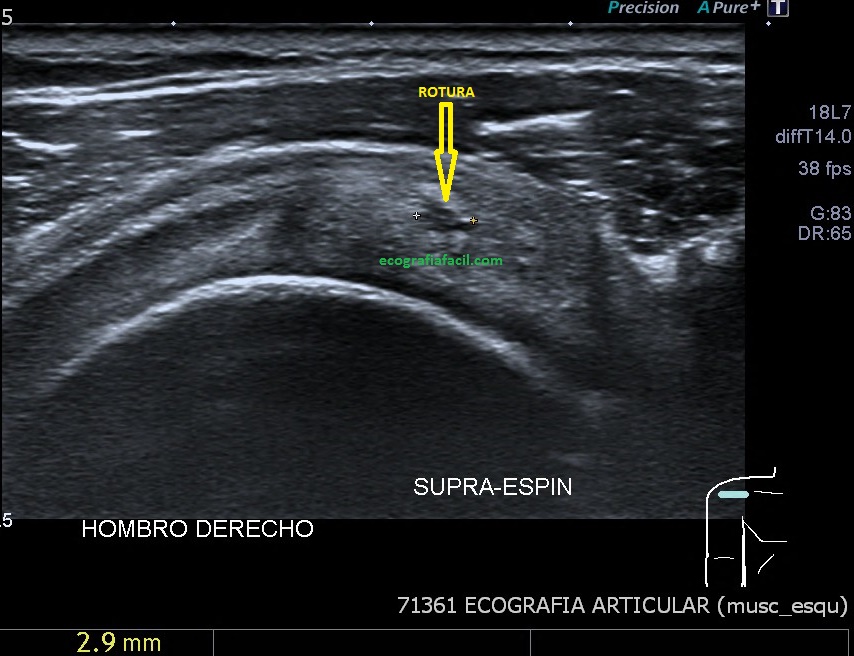

Si tu lo quieres estudiar en un corte transverso o eje corto del tendón verás como muestra de normalidad la imagen número 1. Semiológicamente es muy agradecido. Ves el tendón ovalado, hiperecogénico reposado en la corredera bicipital. El ligamento transverso humeral, hiperecogénico y lineal, anterior a la estructura tendinosa que descansa en la corredera.